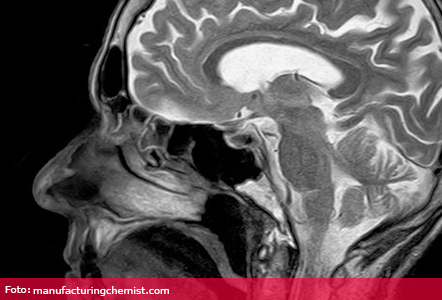

Substanțele de contrast care conțin gadolinium, utilizate în imagistică prin rezonanță magnetică, ar putea fi retrase de pe piață, după ce au fost acumulate suficiente dovezi că substanța se menține în țesutul cerebral, chiar și după mai multe luni de la ultima administrare. Decizia aparține Comitetului de evaluare a riscurilor și farmacovigilență a Agenției Europene a Medicamentului (PRAC) care a recomandat suspendarea autorizației de punere pe piață pentru aceste substanțe.

De fapt, despre consecințe directe este greu de discutat, având în vedere că simptome sau afecțiuni legate de acumularea de gadolinium nu au fost raportate. Până la acest moment există dovezi clare că substanța se menține în țesuturile creierului chiar și două luni, însă informațiile despre efectul pe termen lung sunt limitate.